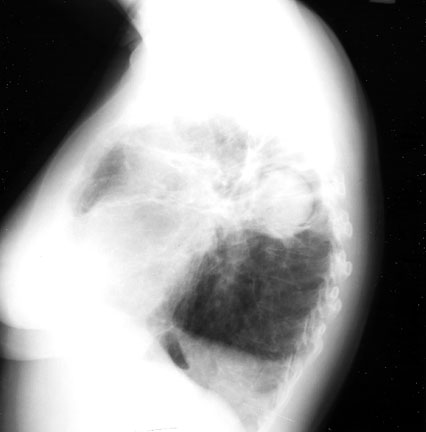

Halo Sign

In a cavity with fungus ball there is a crescentic lucent space along the upper portion of a density giving the appearance of a halo. This phenomenon is seen with two clinical presentations of pulmonary aspergillosis, fungous ball and necrotizing subacute pneumonia during recovery phase from leukopenic episodes.